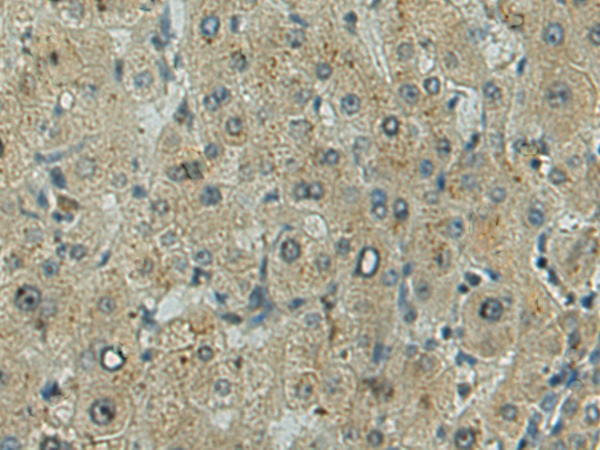

IHC positive control: |

Human liver cancer |